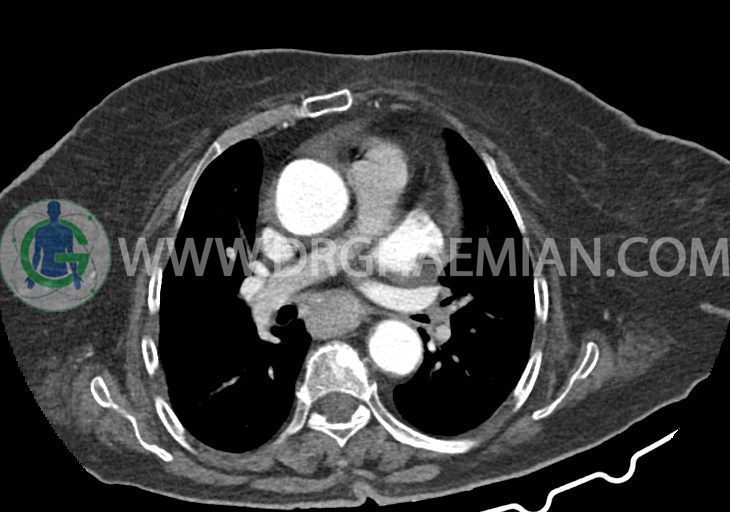

در سی تی اسکن اسپیرال ریه و مدیاستن – شکم و لگن با و بدون کنتراست خوراکی و وریدی (مولتی دیدکتور 16 با مقاطع ظریف و بازسازی های ساژیتال و کرونال):

–کاردیومگالی همراه با pericardial effusion خفیف

–دیلاتاسیون نیمه فوقانی مری توراسیک ناشی از افزایش ضخامت circumferential توده مانند در یک سوم دیستال مری به طول 50mm ، که می تواند مطرح کننده انفیلتراسیون تومورال همراه با تنگی

–آئورت صعودی دیلاته به قطر 38mm